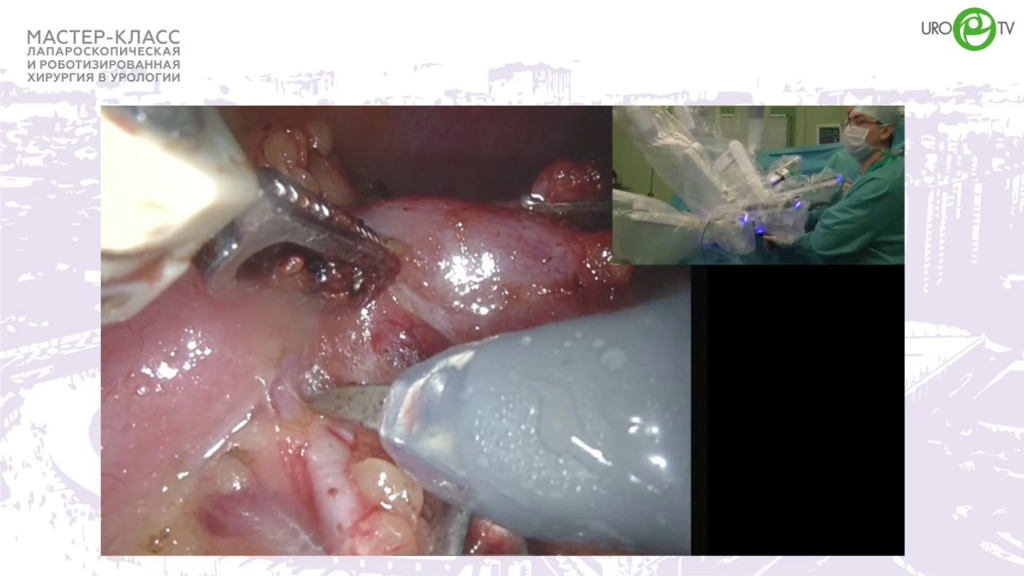

Ракул - Робот-ассистированная резекция почки R.E.N.A.L.-11

11 янв 2022